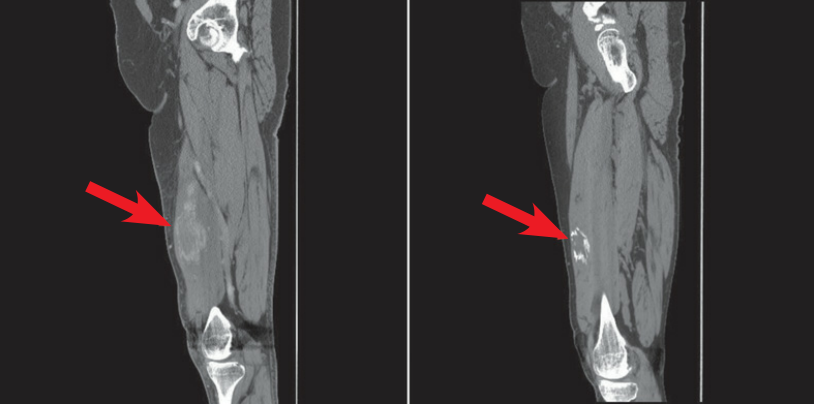

CT 检查:左图异位骨化最初表现为软组织肿块,周围组织水肿,肿块充血周边密度增高,右图患者 4 个月后复查可见局部软组织机化变厚,肿块较前减小但周围见环样骨化。